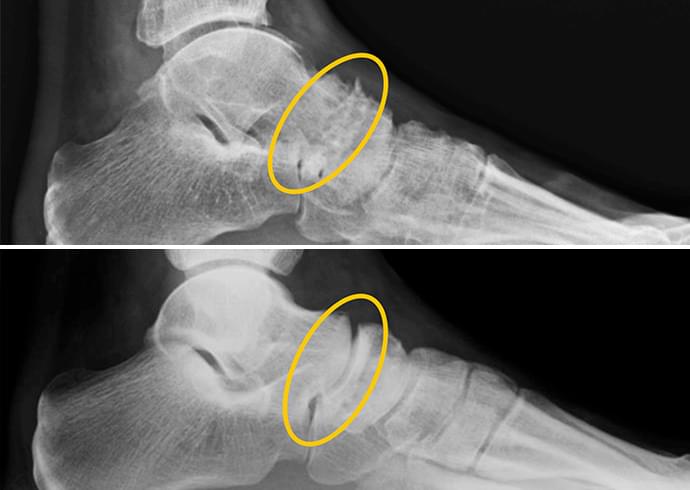

Bokalövés. Fent: arthrosis jelei.

Lent: egészséges ízület a Nautubone gél alkalmazása után